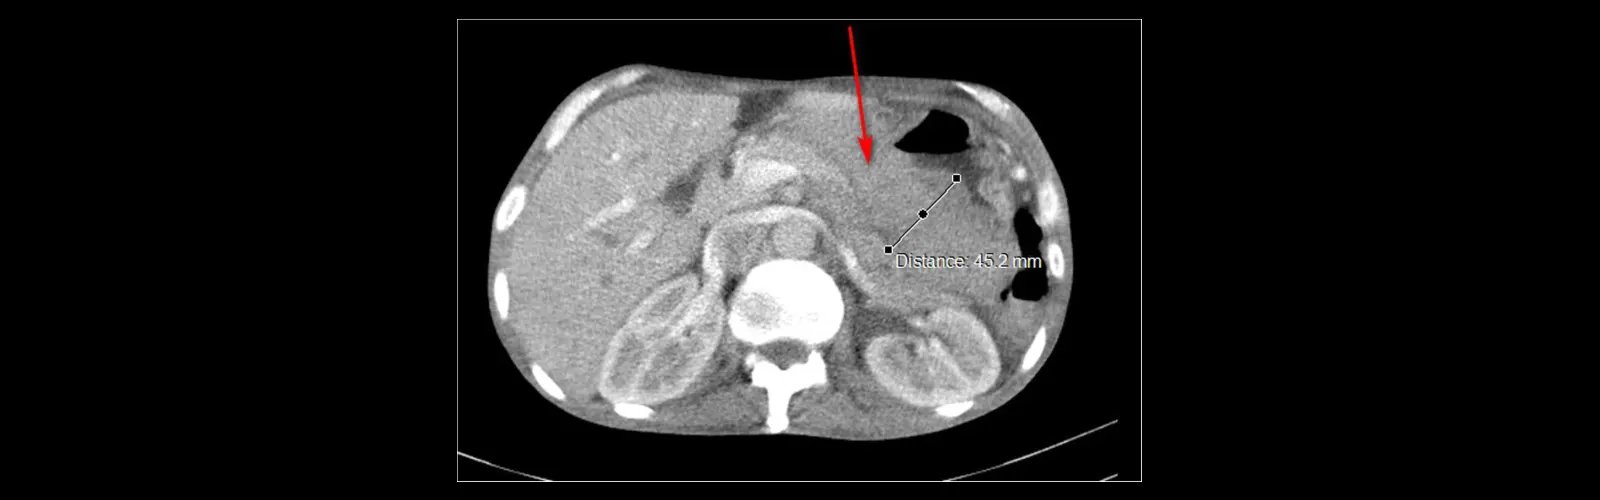

The scanner takes more than one X-ray pix from distinctive angles, which are then processed with the aid of a laptop to create cross-sectional snapshots of the abdomen.

These snapshots can grant treasured data about the liver, kidneys, spleen, pancreas, intestines, blood vessels, and different buildings inside the stomach cavity.

CECT Abdomen is often used to diagnose and consider stipulations such as tumours, infections, inflammation, trauma, kidney stones, stomach pain, and abnormalities in the stomach organs.

CECT stomach can assist decide the traits of tumours hundreds located in the abdomen. The distinction dye highlights the vascularity of the lesion, helping in distinguishing between benign and malignant tumours, ass nicely assessing the extent of tumour involvement.